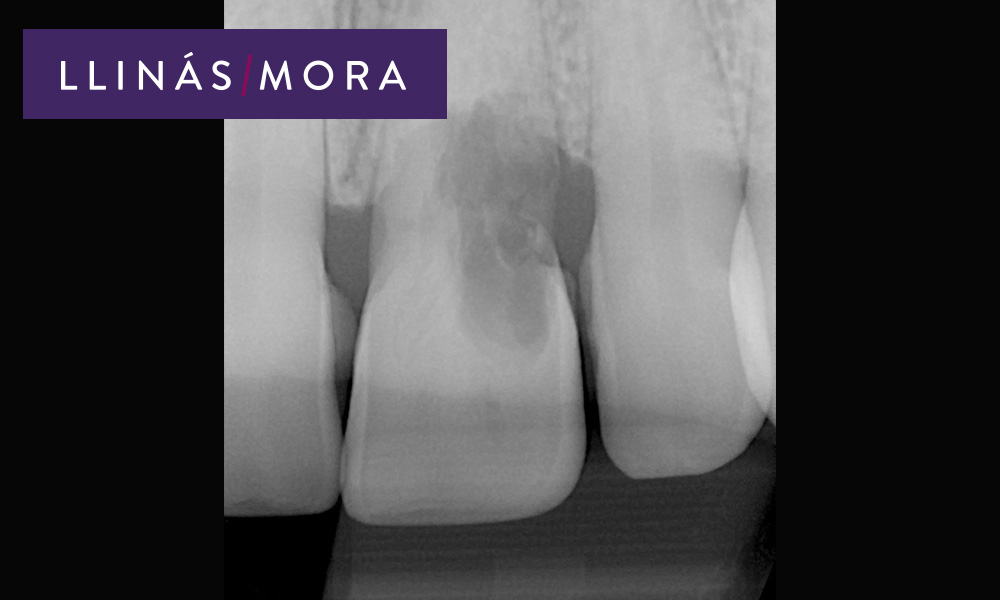

1. Diente con resorción interna. Necesario la exodoncia del mismo